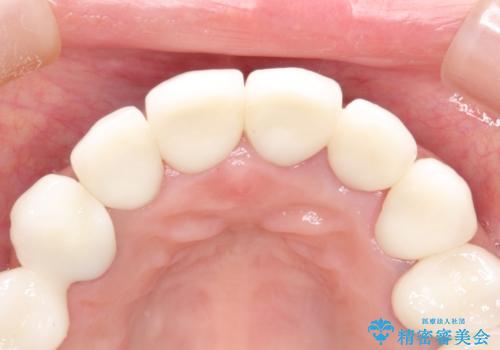

セラミックのかぶせ物だけで、歯並びまで変えようとするのには限界があります。

今回矯正治療で歯並びを整えた後に、セラミックを装着することにより、審美的・機能的に優れた仕上がりにすることができました。